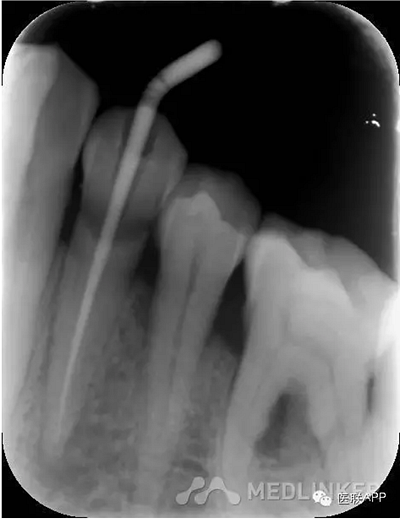

初診:頰側(cè)去腐,合面常規(guī)開髓揭頂,拔髓,電測(cè)根長WL=22mm,EDTA下手?jǐn)U+機(jī)擴(kuò)+protaper根備至F2,CR反復(fù)沖洗,干燥,Vitapex根充,ZOE暫封,約日復(fù)診。